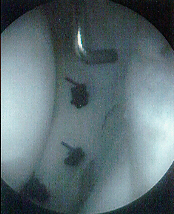

Partial Meniscectomy

- Principle is to preserve as much of functioning rim of meniscus as

possible

- McGinty et al- compared 89 total with 39 partial meniscectomies with

5.6 year follow-up- better results with partial meniscectomy- too soon

to tell

- Indications- Tear patterns not amenable to repair-tears in avascular

zone, small radial tears, and parrot-beak tears